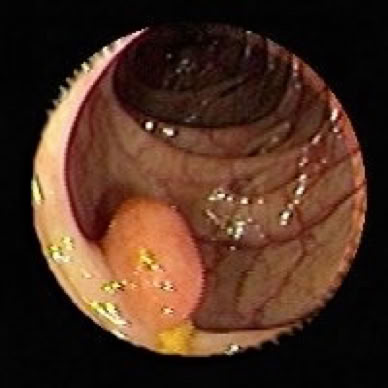

• Darmpolypen (meist gutartige Wucherungen)

• Bösartige Darmerkrankungen (Darmkrebs, der oft aus Polypen entsteht)

Darmpolyp